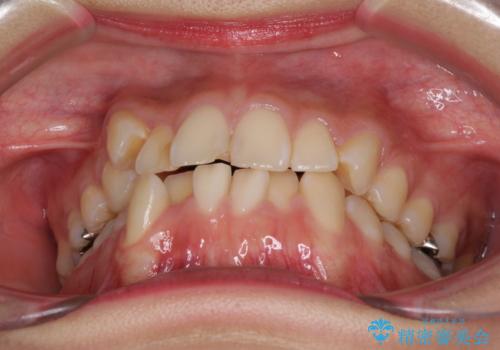

- 上下の八重歯を気にして来院された患者様です。

上下ともに八重歯の後ろの歯を1歯ずつ抜歯し、補助装置(リンガルアーチ)を用いて八重歯の位置を改善し、その後インビザラインにより矯正治療を行うこととしました。

途中海外留学をされたため、治療期間は長くなりましたが、事前に補助装置やワイヤー装置を併用したことで、きれいな歯列に仕上げることができました。